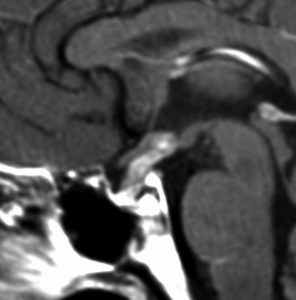

ICE化学療法投与開始から数日で小さくなります

この例は古いので第3脳室開窓術 ETV をしていません。左はICE化学療法前。中央は9日後。右は25日後です。閉塞性水頭症があっても1週間くらいで中脳水道が通って水頭症は改善します。ジャーミノーマであれば,ICE化学療法1コースでかなり縮小するはずです。このような顕著な効果がない時には,逆にジャーミノーマ以外の胚細胞腫瘍が混在していると考えた方がいいでしょう。多くは奇形腫の混在です。